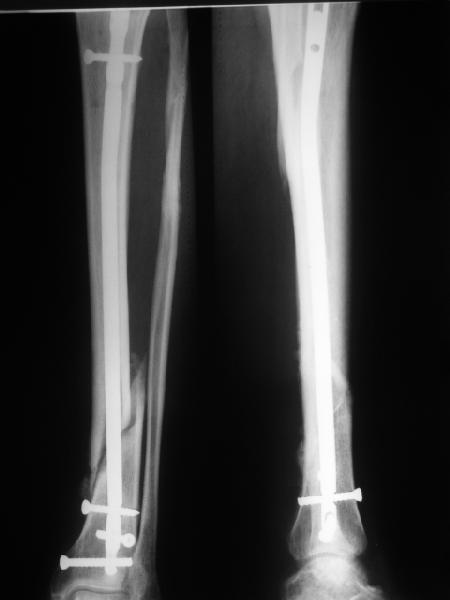

В Кемпбелле можно прочитать, что Fractures in the distal third of the tibia had the highest frequency of nail breakage.

Вообще, этот вопрос обсуждался давно, и еще в статье R. Bucholz (1987) про переломы гвоздей указывалось, что расстояние от ближайшего отверстия до перелома должно быть не менее 5 см, иначе есть угроза усталостного перелома. По литературе переломы гвоздей в нижней трети

tibia достигают 4,3%.